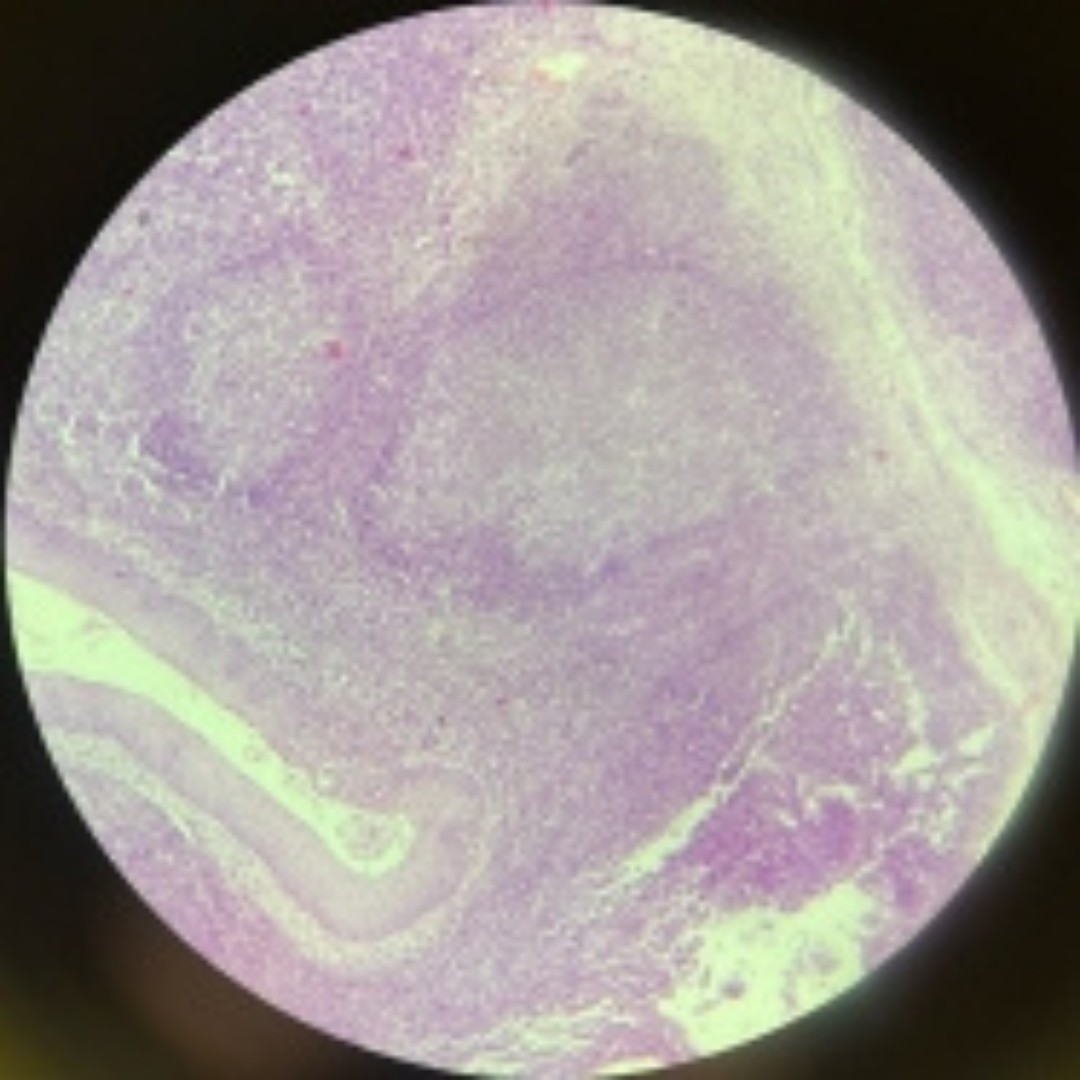

16

New cards

Tonsil

17

New cards

Tonsil

18

New cards

Tonsil

19

New cards

Tonsil